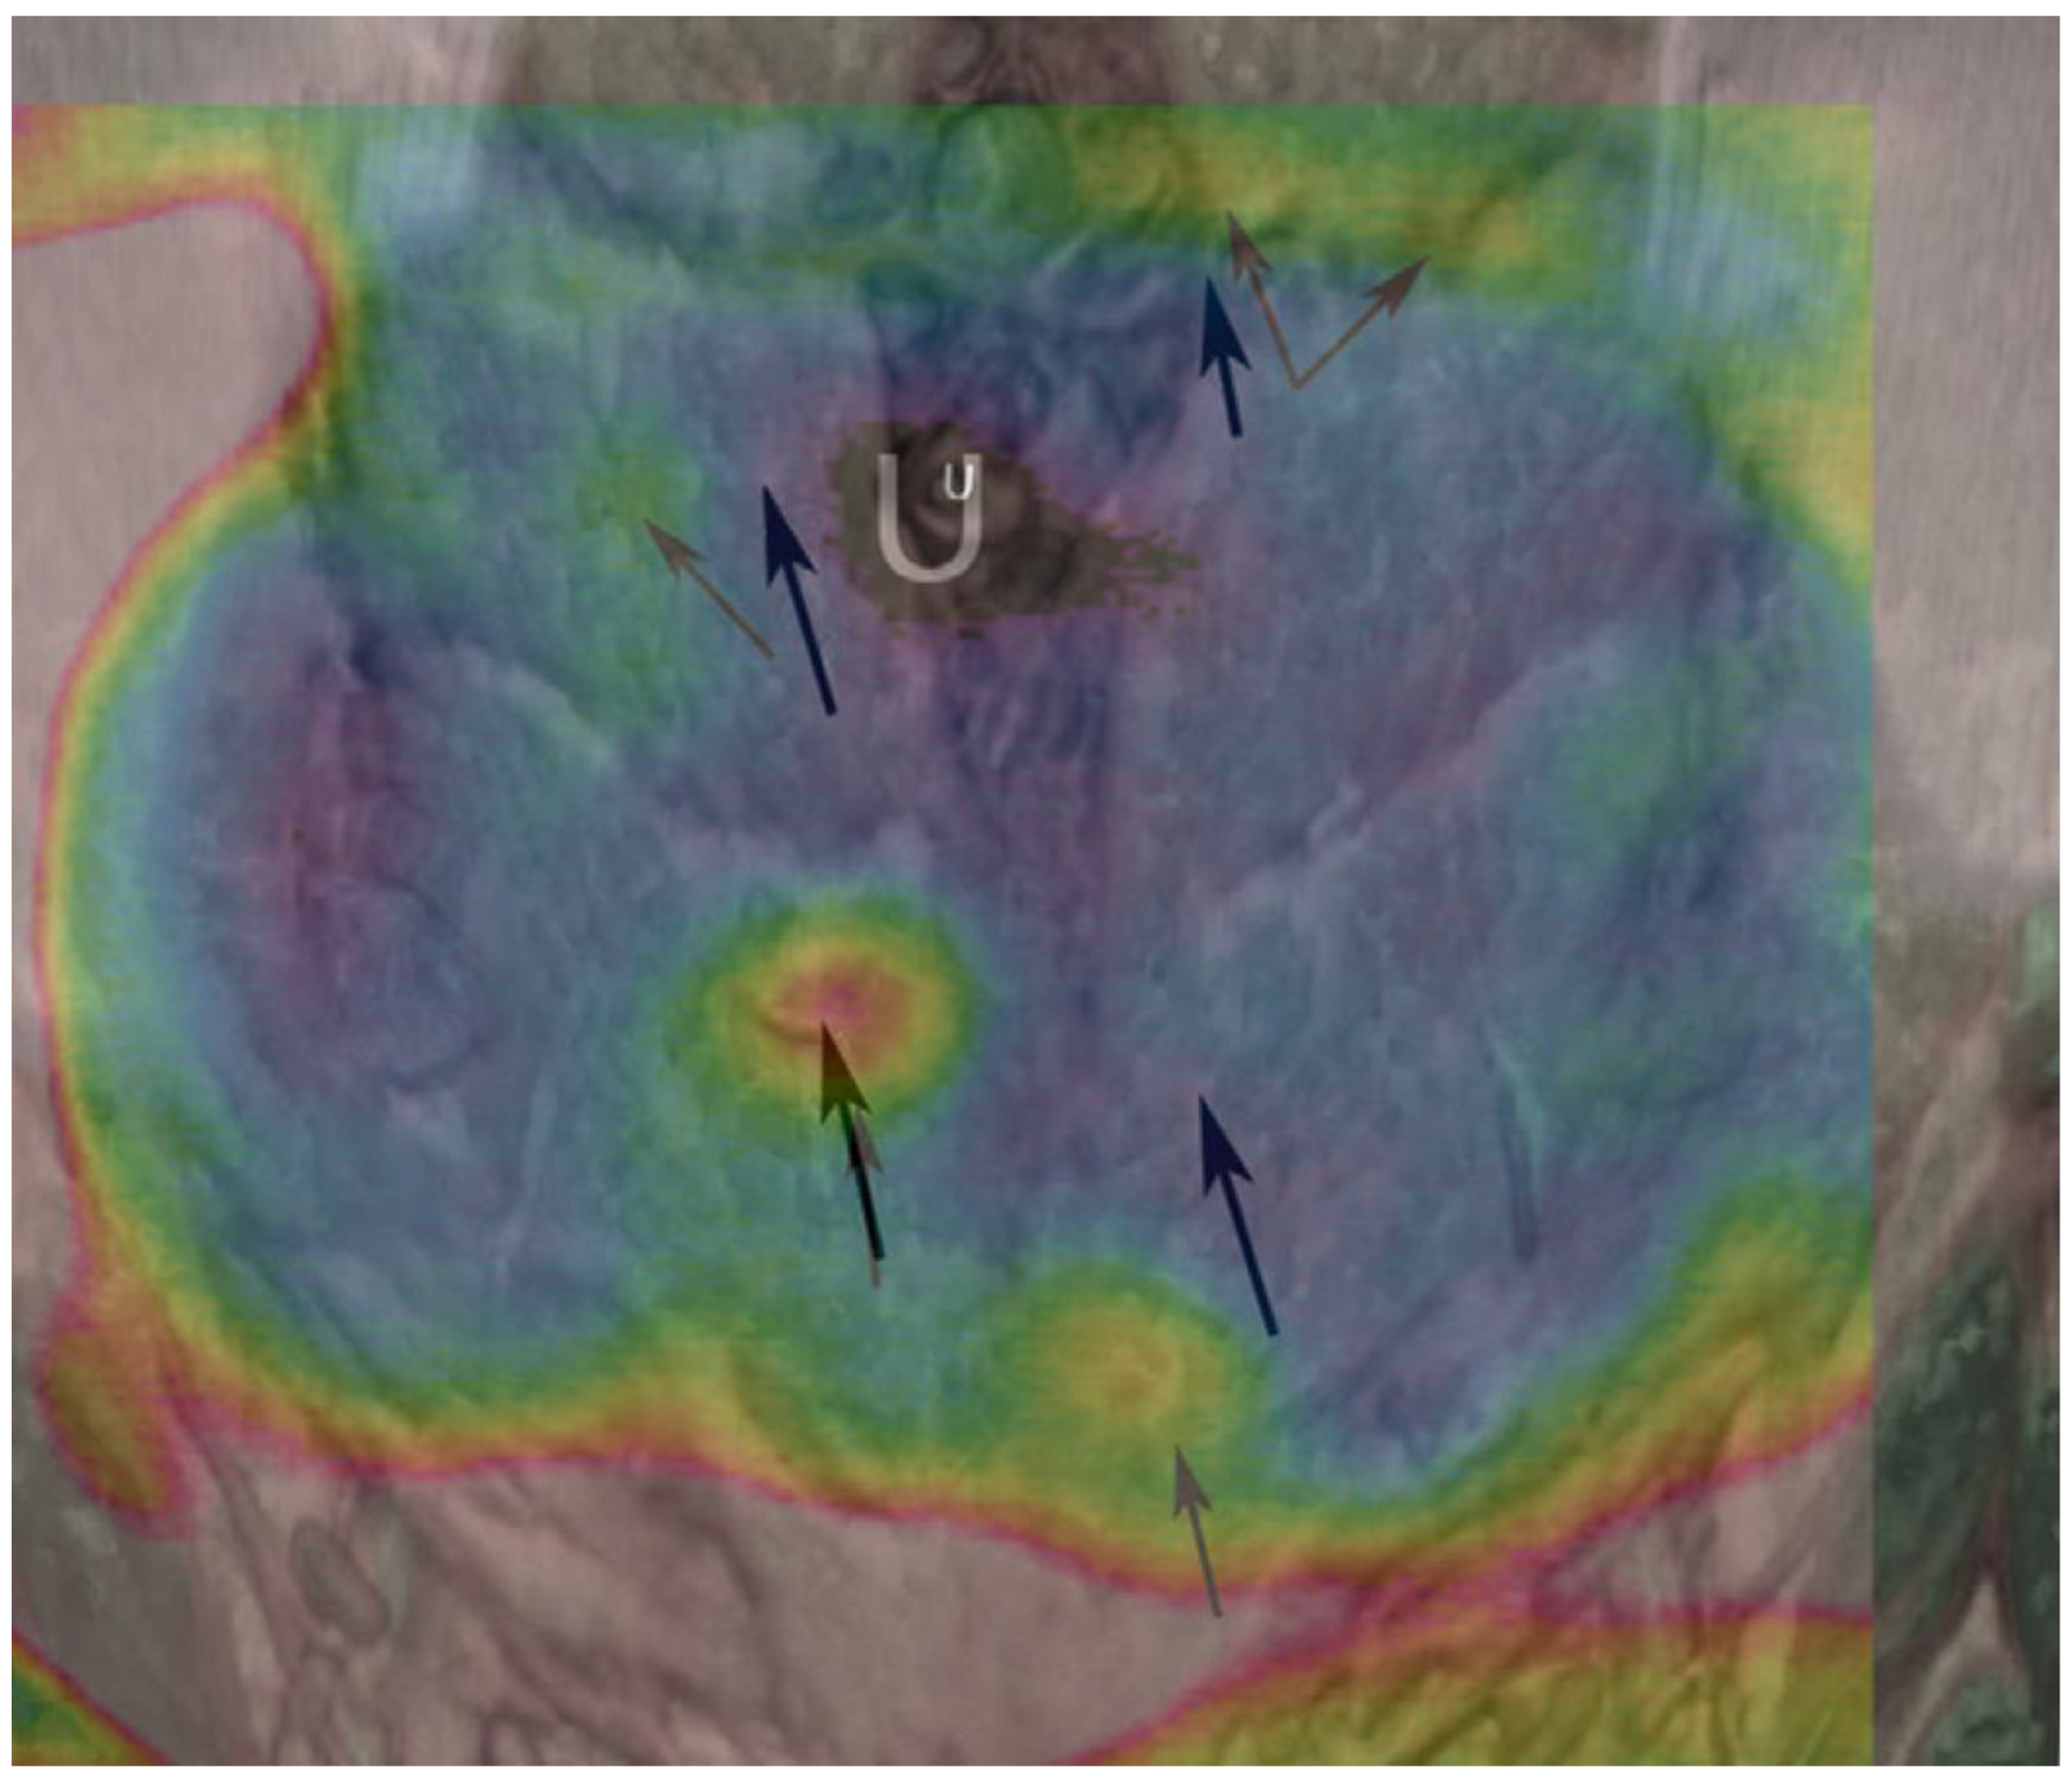

- de Weerd, L.; Weum, S.; Mercer, J.B. The value of dynamic infrared thermography (DIRT) in perforatorselection and planning of free DIEP flaps. Ann. Plast. Surg. 2009, 63, 274–279. [Google Scholar] [CrossRef] [PubMed]

- Whitaker, I.S.; Lie, K.H.; Rozen, W.M.; Chubb, D.; Ashton, M.W. Dynamic infrared thermography for the preoperative planning of microsurgical breast reconstruction: A comparison with CTA. J. Plast. Reconstr. Aesthet. Surg. 2012, 65, 130–132. [Google Scholar] [CrossRef]

- Weum, S.; Mercer, J.B.; de Weerd, L. Evaluation of dynamic infrared thermography as an alternative to CT angiography for perforator mapping in breast reconstruction: A clinical study. BMC Med. Imaging 2016, 16, 43. [Google Scholar] [CrossRef]

- Hennessy, O.; Potter, S.M. Use of infrared thermography for the assessment of free flap perforators in autologous breast reconstruction: A systematic review. JPRAS Open 2020, 23, 60–70. [Google Scholar] [CrossRef] [PubMed]